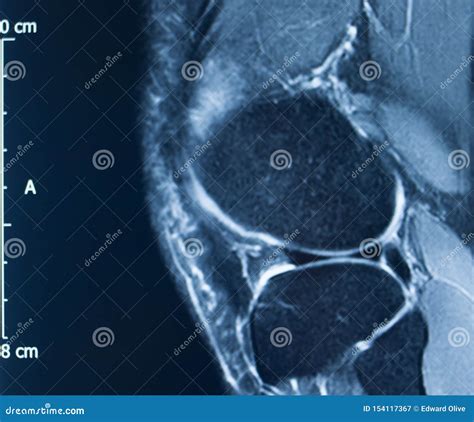

Diagnosing an MCL Tear with an MRI

An Mcl Tear Mri is a non-invasive imaging technique that provides detailed images of the knee joint. MRI uses magnetic fields and radio waves to create cross-sectional images of the body’s internal structures. This allows healthcare professionals to visualize the MCL and other soft tissues in the knee, identifying any tears or damage.

During an *Mcl Tear Mri*, the patient lies on a table that slides into a large, cylindrical machine. The procedure is painless and typically takes about 30-60 minutes. The MRI machine captures multiple images from different angles, providing a comprehensive view of the knee joint.

An *Mcl Tear Mri* can help determine the grade of the MCL tear, which is classified as follows:

An *Mcl Tear Mri* is particularly useful for differentiating between an MCL tear and other knee injuries, such as meniscal tears or anterior cruciate ligament (ACL) injuries. This information is crucial for developing an appropriate treatment plan.